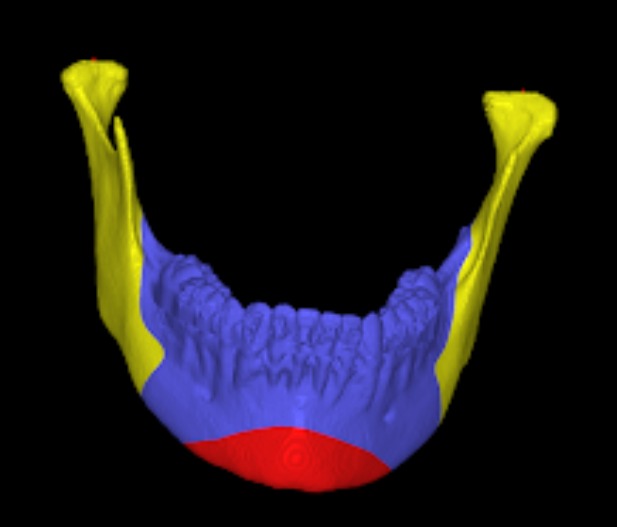

Le Fort Osteotomy Procedures

- Le Fort I Osteotomy: A procedure that separates the upper jaw from the rest of the facial bones, which facilitates repositioning it forward, backward, superiorly (upward), or inferiorly (downward), thereby creating a better facial appearance.

- Pre-surgical Orthodontics: Often needed before the actual surgery takes place. Imaging: X-rays and CT scans are required.

- Planning: Virtual surgical planning is performed on a computer, along with model surgery.